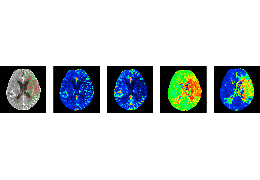

成像智能。

Eclipse 成像智能功能提供强大的处理能力和最佳质量的影像,同时减少质量错误并提高剂量效率。

凭借 AI、专有算法和先进的影像处理能力,提供出色的影像质量和无与伦比的诊断信心。